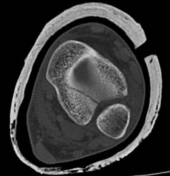

Standard orthogonal radiographs (anteroposterior and lateral) are insufficient for evaluating tibial fractures with suspected plafond extension. A dedicated computed tomography (CT) scan of the ankle with coronal, sagittal, and 3D reconstructions is mandatory.

Image

The CT scan serves several critical functions. First, it identifies the exact location and orientation of the articular split. Second, it dictates the trajectory of the independent articular lag screws, ensuring they are placed perfectly perpendicular to the fracture plane. Third, and perhaps most importantly, it allows the surgeon to map the safe zones for these lag screws so they do not obstruct the planned path of the intramedullary nail.